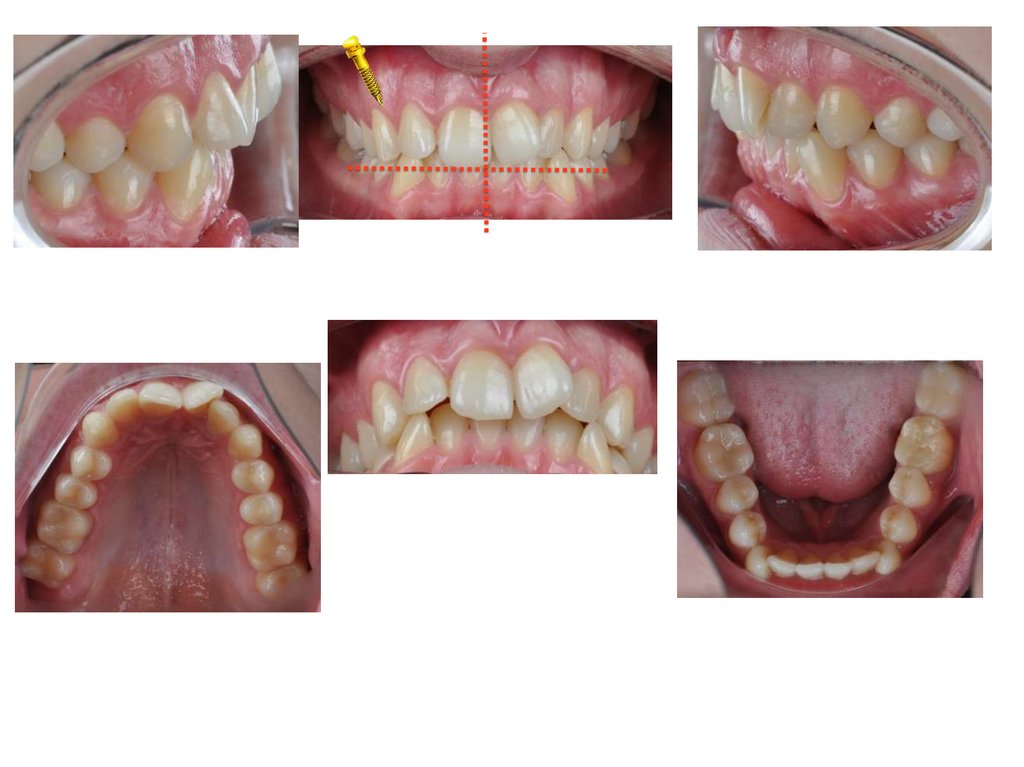

Нормализация положения зубов

1.Нормализация положения

зубов

2. Выведение нижнего и

верхнего фронта из ретрузии

3.Сепарация фронт верх и низ

4. Минивинт 1 сегмент?